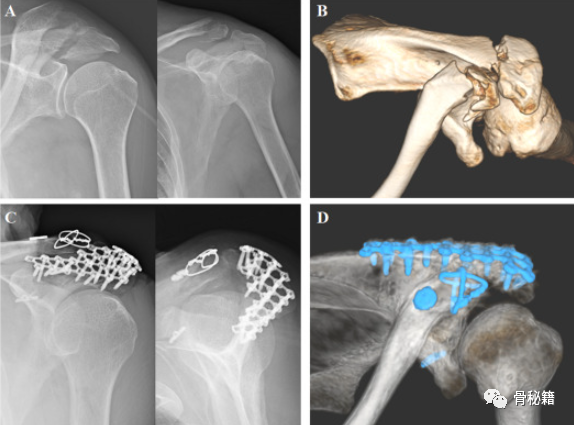

肩峰粉碎骨折,采用钢板螺钉固定,完成悬吊复合体的稳定

肩峰骨折 移位明显,采用钢板固定

如果怀疑肩胛锁骨连杆 (SSSC) 中断,则应拍摄负重 AP 影像。如果肩峰骨折是肱骨头外伤性上移位或肱骨近端慢性上移的结果,则应考虑长期存在的肩袖疾病(例如,肩袖撕裂性关节病伴应力肩峰骨折)